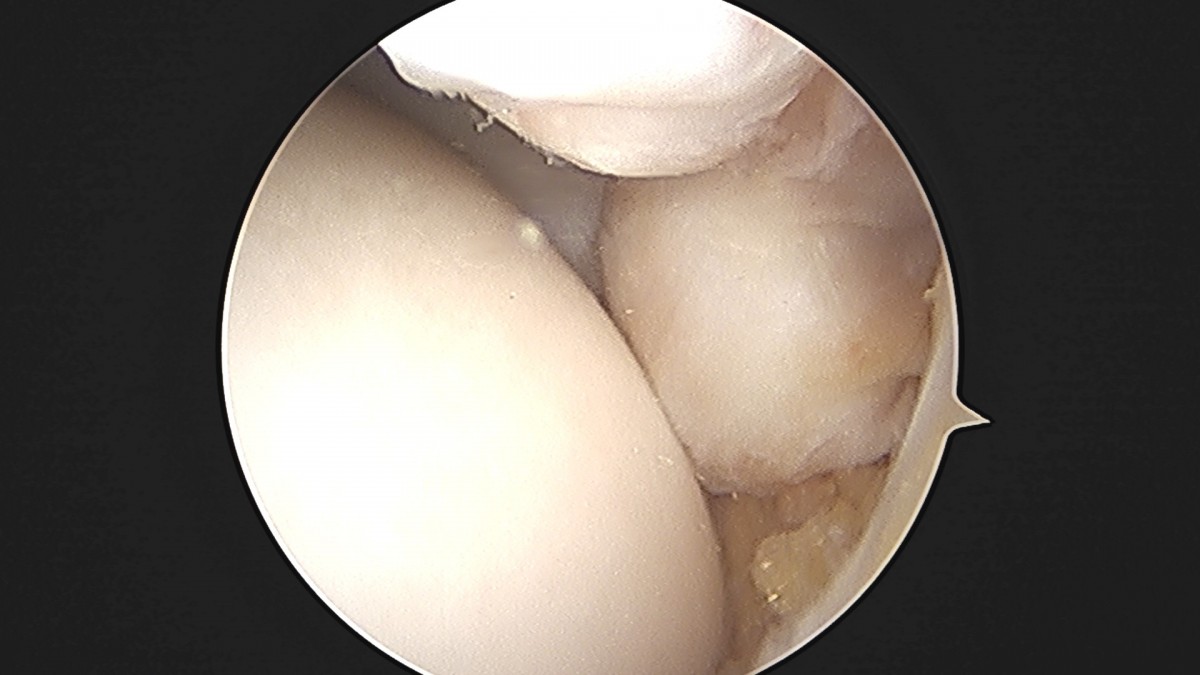

이재상원장님 발목 활액막 절제술 및 인대 봉합술 정보O 환자

작성자 최고관리자 댓글 0건 조회 797회 작성일 25-09-16 15:23